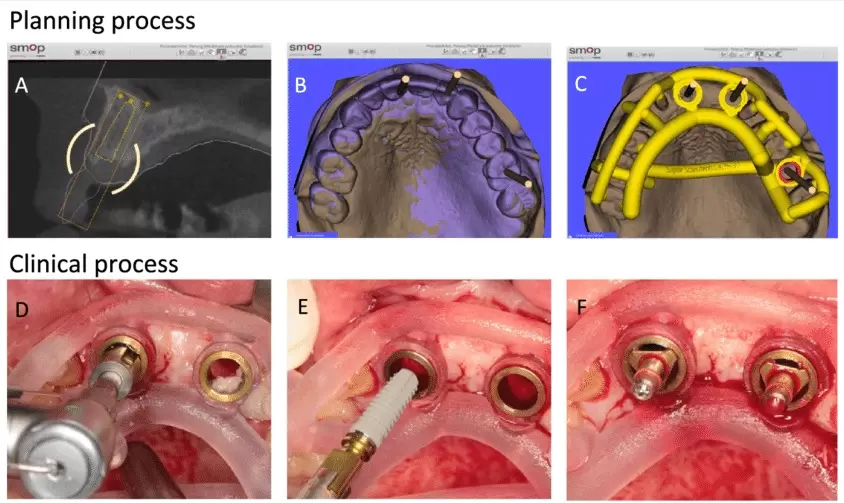

Đầu tiên trong Quy Trình Trồng Răng Implant. Bệnh nhân sẽ tiến hành chụp phim CT Conebeam và Scanning răng, chụp ảnh trong và ngoài miệng. Từ các dữ liệu thu thập được sẽ đưa vào vào phần mềm Exocad để lập kế hoạch điều trị. Với khả năng phân tích về lực. Phần mềm Exocad cho phép bác sĩ tính toán chính xác vị trí cũng như hướng đặt implant.

Sau khi hoàn tất quá trình lập kế hoạch trên phần mềm. Một máng hướng dẫn sẽ được sản xuất nhằm mục đích đặt trụ implant chính xác. Tránh làm tổn thương các cấu trúc lân cận, tổn thương ống dây thần kinh răng dưới hay xoang hàm… Đồng thời, mô nha chu cũng được tái lập giả định trên trạng thái lý tưởng. Sau đó một trụ lành thương giải phẫu cá nhân hóa sẽ được sản xuất cùng với máng hướng dẫn.

Máng Hướng Dẫn Phẫu Thuật Guideline – Đảm Bảo An Toàn Và Chính Xác Tuyệt Đối

Để đảm bảo độ chính xác cao trong quá trình cấy ghép. Chúng tôi sử dụng máng hướng dẫn phẫu thuật chuyên biệt. Máng này được thiết kế riêng cho từng bệnh nhân, dựa trên hình ảnh 3D của xương hàm. Giúp bác sĩ định hướng và đặt trụ Implant chính xác vào vị trí mong muốn. Nhờ đó, thời gian phẫu thuật được rút ngắn, giảm thiểu nguy cơ biến chứng. Đảm bảo kết quả ổn định, lâu dài.

Những ưu điểm khi đặt trụ implant bằng máng hướng dẫn phẫu thuật Guideline.

- Ưu điểm thứ nhất: An toàn tuyệt đối.

Guideline đảm bảo trong quá trình khoan mũi khoan không bị lệch, không bị khoan quá nông hay quá sâu. Từ đó ngăn chặn các biến chứng do việc lệch mũi khoan gây nên.

- Quá trình phẫu thuật diễn ra nhanh hơn, nhẹ nhàng và ít đau hơn.

Do vị trí cắm implant đã được định vị trên máng. Nên khi sử dụng Guideline, bác sĩ sẽ không cần lật vạt lợi quá rộng. Quá trình khoan cũng không cần phải ngắm điều chỉnh. Phẫu thuật sẽ diễn ra nhanh chóng hơn, nhẹ nhàng hơn. Ít sưng đau và chảy máu hơn so với phương pháp đặt trụ dựa vào kinh nghiệm và cảm giác tay (freehand).

Khi máng hướng dẫn và trụ lành thương đã được sản xuất cá nhân hoá. Bệnh nhân sẽ được hẹn tới nha khoa để tiến hành phẫu thuật đặt implant. Thông thường, quy trình trồng răng implant DCT có sự hỗ trợ của máng hướng dẫn sẽ diễn ra nhanh chóng. Nhẹ nhàng chỉ khoảng 10 phút/trụ.